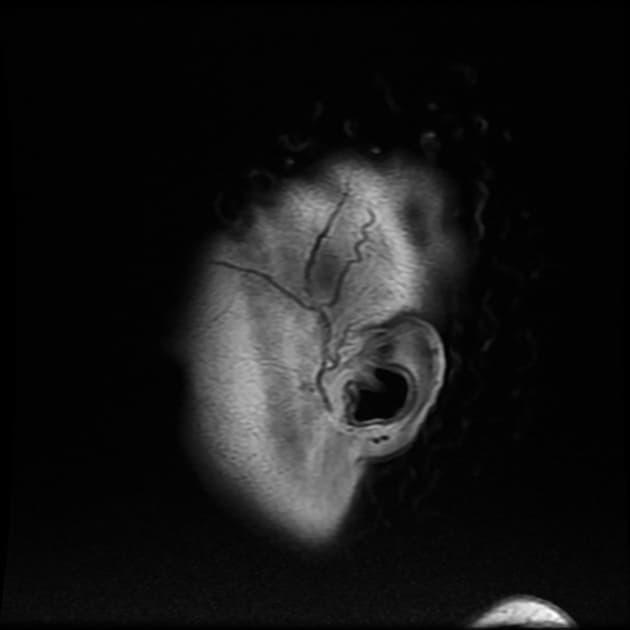

Axial FLAIR

- Nhiều vùng tín hiệu tăng trên T2/FLAIR ở vùng dưới và trên lều tiểu não, chủ yếu tại chất trắng vùng trên lều, kèm các ngón Dawson điển hình.

- Các ổ tín hiệu tăng trên T2/FLAIR khác được ghi nhận tại thể trai của thể chai, đồi thị trái, bán cầu tiểu não trái.

- Các tổn thương cận vỏ não tại thùy đỉnh trái và thùy chẩm trái.

- Một số tổn thương biểu hiện hạn chế khuếch tán (restricted diffusion) tại thùy đỉnh trái và chất trắng quanh thất bên phải.

- Teo não toàn thể, mỏng thể chai, và giãn não thất (ventriculomegaly).

- Những thay đổi rộng rãi trên T2/FLAIR kèm teo não (atrophy) về thể tích, phù hợp với chẩn đoán xơ cứng rải rác giai đoạn tiến triển (advanced multiple sclerosis).

- "Các ngón Dawson là những tổn thương ở chất trắng quanh thất định hướng vuông góc với thành thất bên, rất điển hình trong xơ cứng rải rác."

- "Tổn thương cận vỏ và ở thể chai, đặc biệt khi có hiện tượng mỏng thể chai, củng cố chẩn đoán xơ cứng rải rác giai đoạn tiến triển."